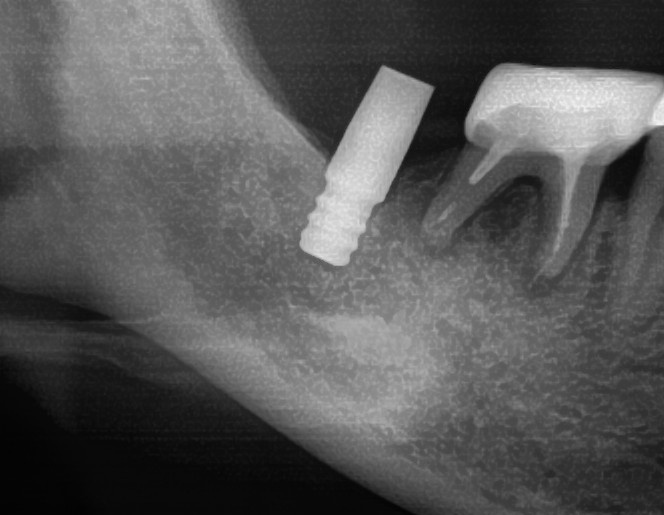

開けた穴に、専用道具を使ってネジを締めるように長さ2センチ程のインプラントを骨に埋め込んでいきます。

しっかりとインプラント埋め込まれた後は、動揺がないか、噛んだ時に当たらないかなどを確認して、最後にパノラマ写真を撮影して今回のオペは終了となりました。